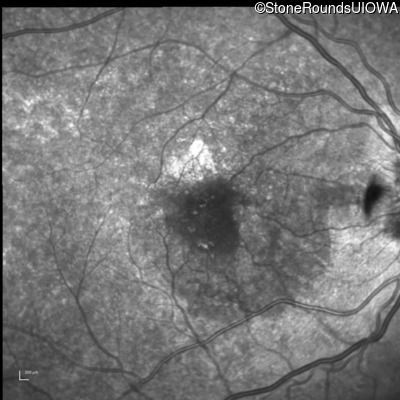

Blue Autofluorescence - Left - 20/20 -2

Exemplar